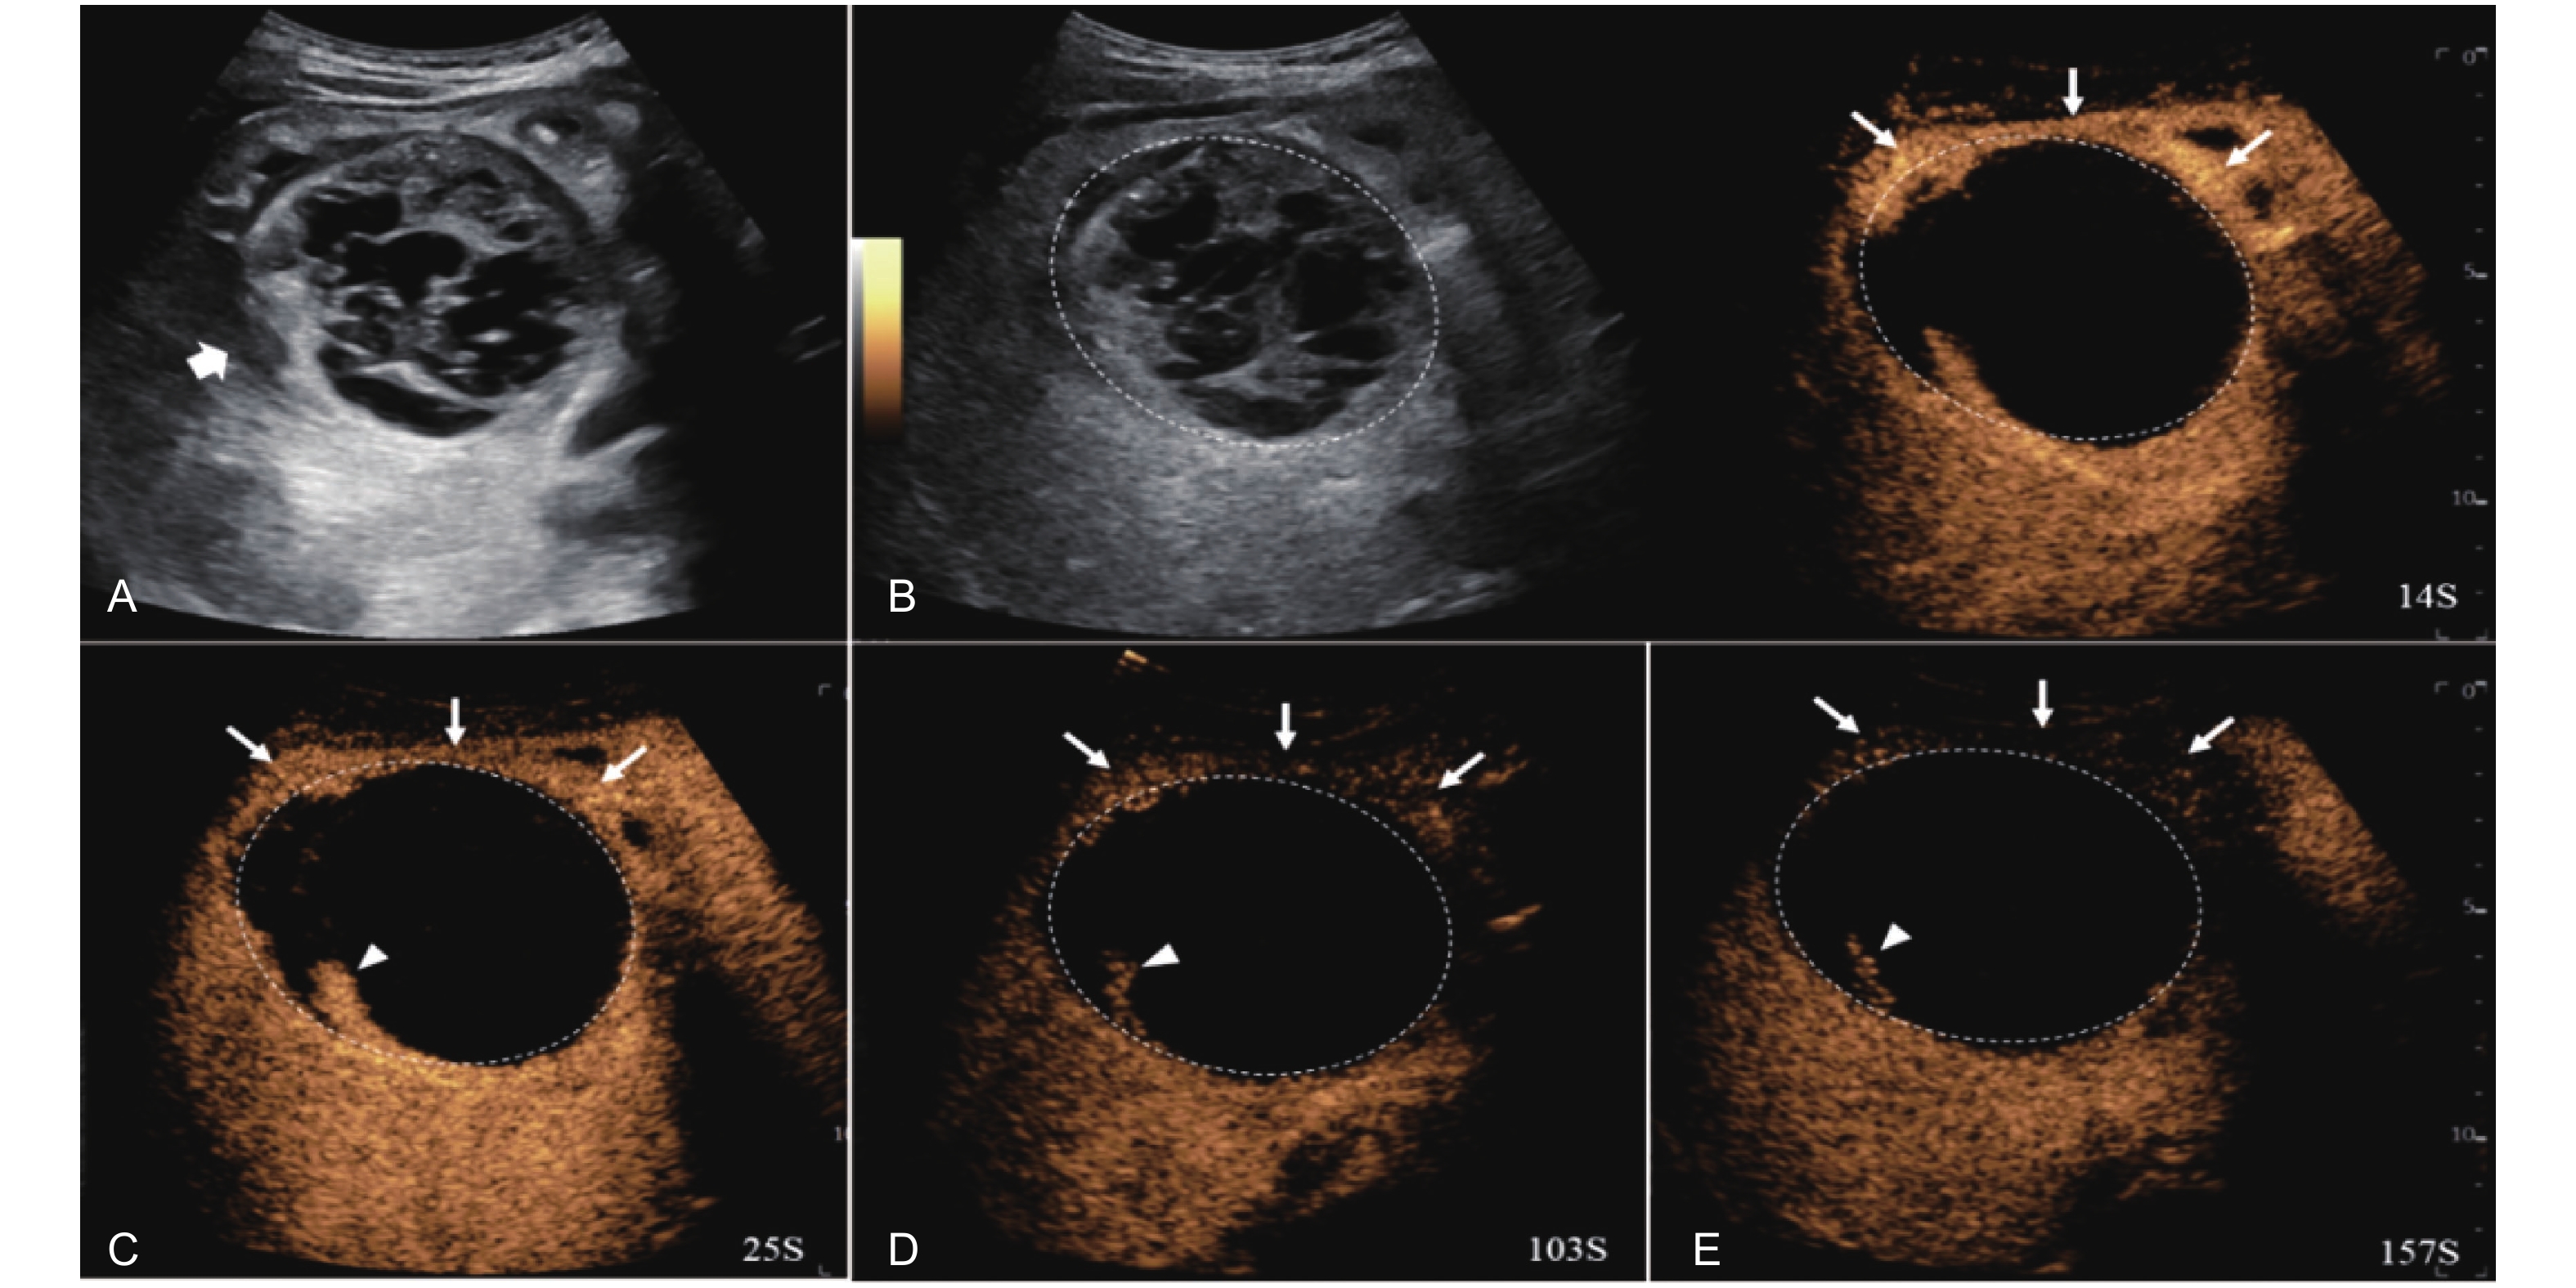

Figure 14

LR-TR Viable. Example of a treated tumor 16 days after TACE. (A) B-mode image shows a cystic-solid heterogeneous echogenic lesion with a peripheral hypoechoic band (thick arrow), measuring 71 mm in segment V and VI; (B-C) CEUS shows intralesional partial hyperenhancement (arrowhead) with perilesional hyperenhancement (thin arrow) during the arterial phase; (D-E) The lesion shows intralesional marked washout (arrowhead) and perilesional partial marked washout (thin arrow) in the portal venous and late phases. Findings are consistent with LR-TR Viable."